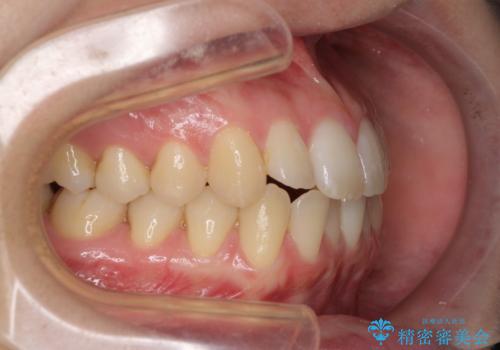

気になる前歯を整えたい インビザライン・ライトでの矯正治療

- ちょっとしたデコボコを整えたいとのことで来院された患者様です。

歯列不正は軽微であったため、インビザライン・ライトにより、費用を抑えて矯正治療を行うこととしました。

上下前歯の捻れが改善され、患者様には大変満足していただきました。